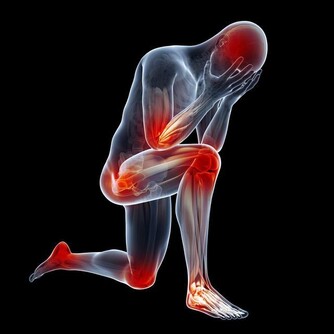

經常「肩膀痛」或「手不舉」嗎?五十肩找上門來怎麼辦?

事實上,五十肩的英文名詞是:「冰凍肩」(frozen shoulders),

它的正確名稱是:「粘連性肩關節囊炎(adhesive capsulitis)」簡單說來,

就是關節囊重複累積各種酸痛、發炎後,最後被僵硬的軟組織夾擊,導致關節無法活動。

雖然這種症狀好發於40-60歲之間的族群,但年齡只是參考,

越來越多人年輕人發現手臂「忽然不舉」,才知道竟然是五十肩發作。